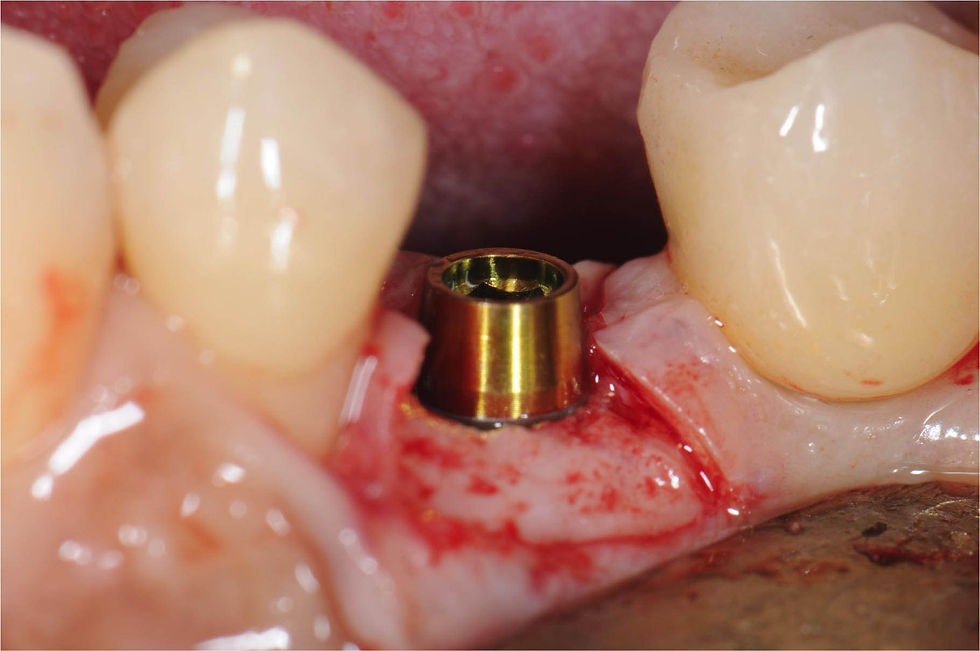

Insertion of the Prama RF implant. Then a Prama IN healing abutment will be placed: it surrounds the implant neck by 0.5 mm.